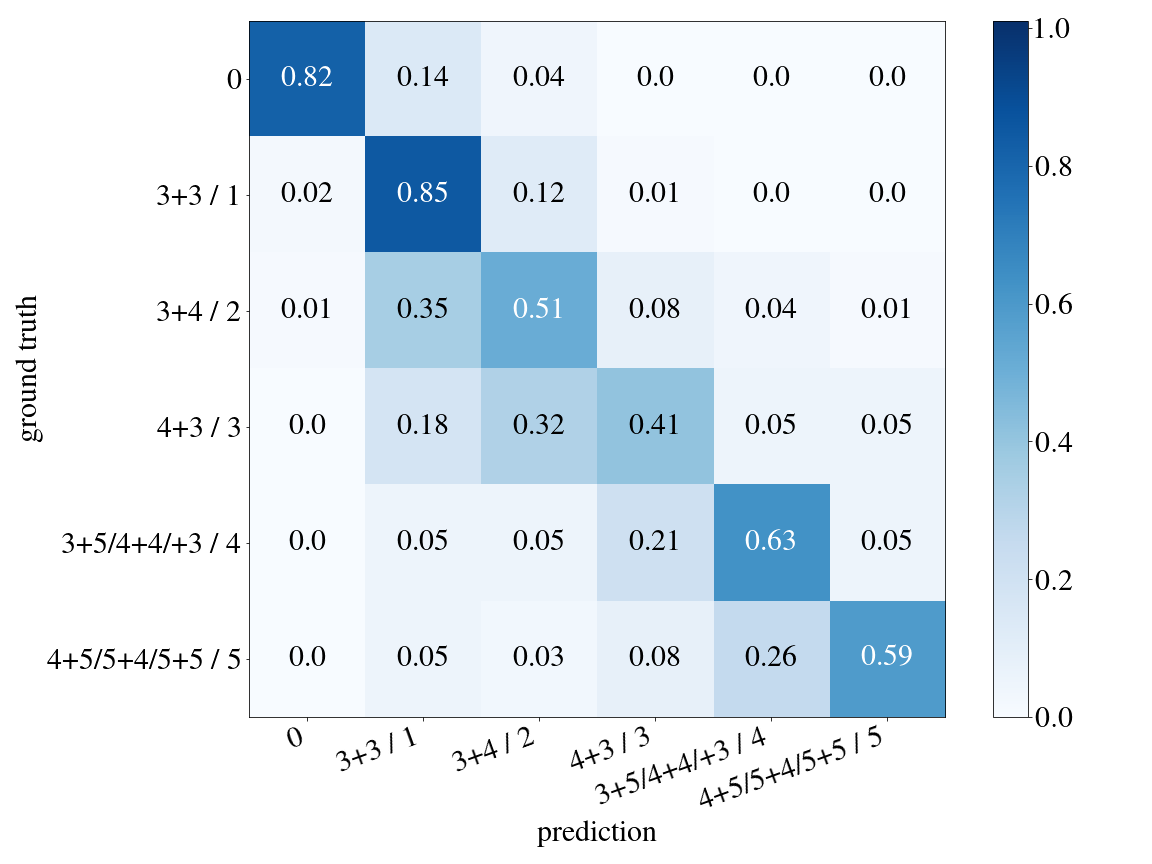

The ISUP classification was trained on 1863 images with 402 validation images of the Gleason dataset (see \figurereffig:apd_model_3_stepsA). The kappa score on the validation set is 0.85. The confusion matrix is shown in \figurereffig:apd_confmatrix.

fig:apd_confmatrix